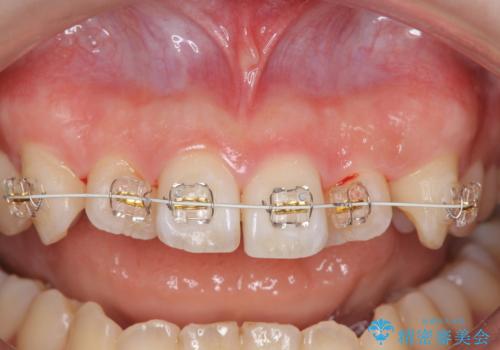

インビザラインの不得意な上顎前歯のねじれの改善を、マウスピース矯正を行う前に前歯のみの部分ワイヤー矯正を行うことで治療期間の短期化を目指します。

上顎前歯のねじれはマウスピースで治りづらいため、マウスピース矯正の治療期間の長期化をきたしやすい歯列不正です。

マススピース矯正を始める前に、部分ワイヤー矯正を行うことで治療の短期間化・良好な仕上がりを達成することができました。